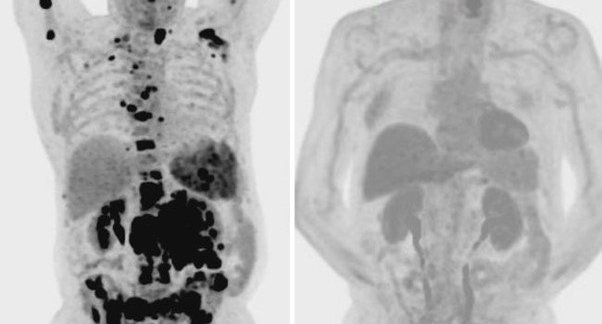

Allan was the fifth patient to undergo CAR T cell therapy at University Hospital Southampton. This groundbreaking treatment re-engineers a patient’s own immune cells to target and destroy cancer.

Sean Lim, Professor of Haematology at the University of Southampton’s Centre for Cancer Immunology, works on developing new immunotherapies. She said: “CAR T cell therapy enables T cells, a type of white blood cell, to recognise cancer cells and attack them. This involves collecting a patient’s T cells and modifying them so that they can recognise the cancer cells. The modified T cells are then reinfused into the patient so that they can kill the cancer cells.”

After five weeks of treatment, Allan’s scans showed no trace of cancer. Now, two years on, he remains in remission – a living testament to the power of innovation in cancer care. He said: “It’s like a miracle cure. I am so grateful to the medical teams who gave me a second chance at life.”